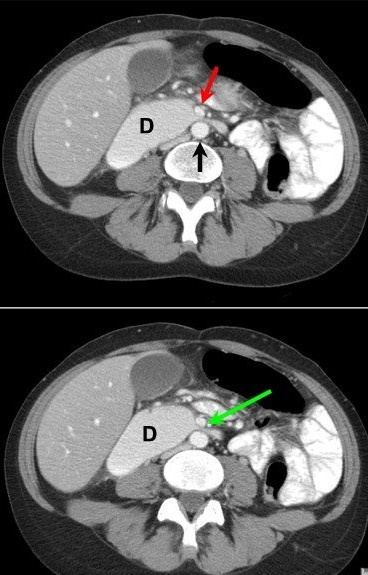

На аксиальных срезах ОБП в венозную фазу исследования отчётливо видно уменьшенное расстояние между аортой (черная стрелка на верхнем изображении) и ВБА (красная и зелёная стрелки): менее 10 мм. D-duodenum, престенотическое расширение нисходящей части и компрессия горизонтального отдела двенадцатиперстной кишки между двумя сосудами (симптом "клюва")